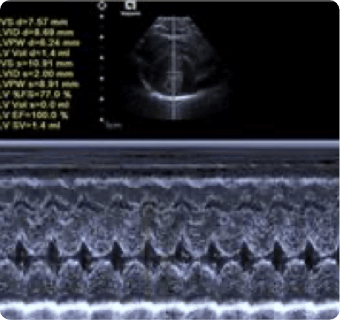

일산시티동물의료센터는 지멘스에서 개발한 고성능 프리미엄 초음파 장비인

Siemens Sequoia를 활용하여 심장, 복부 장기, 림프절 등의 구조물을 선명하게 구현하고,

미세한 해부학적 구조까지 정밀하게 확인할 수 있습니다.

이 장비는 대표적인 심장 질환인 이첨판 폐쇄부전증과 비대성 심근병증,

그리고 선천성 심혈관 질환인 동맥관 개존증, 심방중격결손, 심실중격결손 등을

진단하는 데 사용됩니다.